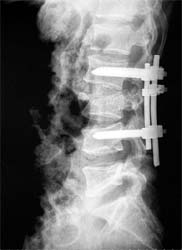

患者男性,30岁,腰3骨折,截瘫

CT显示腰3椎体爆裂,骨块凸入椎管压迫硬膜囊

施行后路椎管前方减压术及经椎弓根固定植骨术,彻底解除 脊髓前方的压迫及后凸畸形,截瘫部分恢复